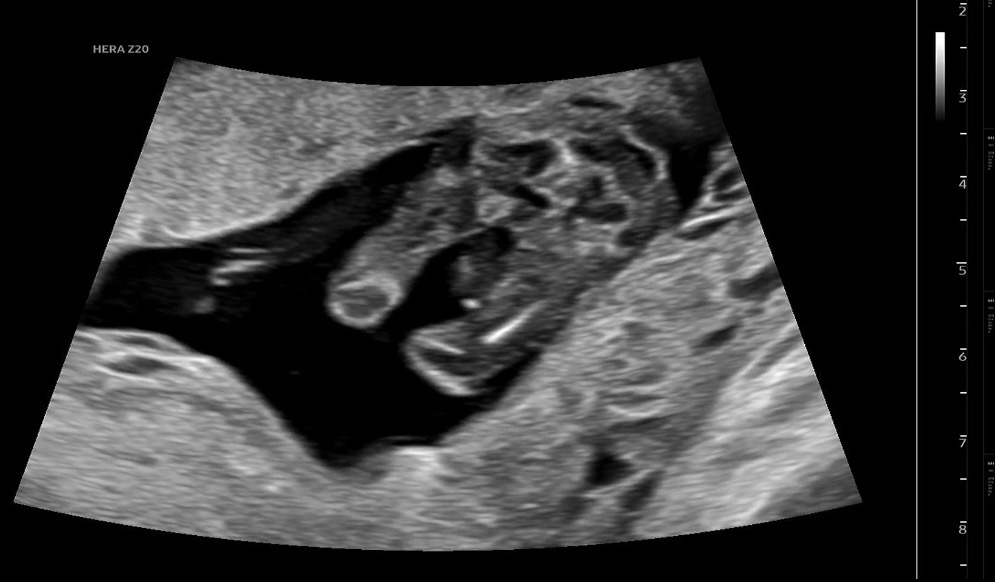

초음파봐주실뿐~~!

다리사이에 뭔가보이는데 아들일까요~~??🥲